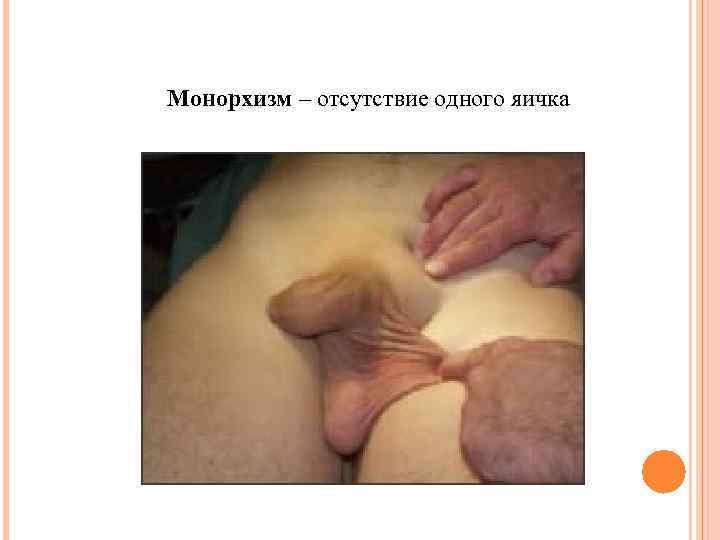

Монорхизм – отсутствие одного яичка

Монорхизм – отсутствие одного яичка